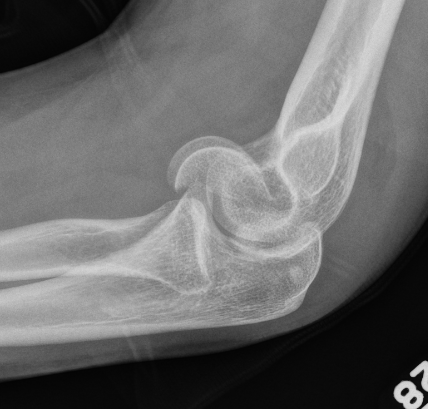

Dubberly Classification

| Type I | Type Ii | Type III |

|

Capitellar fracture

Capitellum + trochlea fracture In one piece Double arc sign seen on xray |

Capitellum + trochlea fractures In two separate pieces |

Double arc sign on xray |